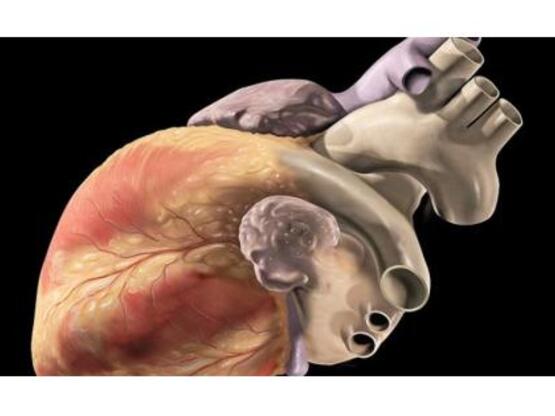

Η θεραπεία με PRP αποτελεί μία μέθοδο κατά την οποία υψηλή συγκέντρωση αιμοπεταλίων λαμβάνεται με ειδική επεξεργασία και τεχνική από το ίδιο το αίμα του κάθε ασθενούς και εν συνεχεία εγχέεται στην πάσχουσα περιοχή. Τα αιμοπετάλια είναι κύτταρα τα οποία εκτός από τη συμμετοχή τους στην πήξη του αίματος διαθέτουν και ένα σημαντικό αριθμό αυξητικών παραγόντων οι οποίοι διαδραματίζουν ενεργό ρόλο στη διαδικασία της επούλωσης των ιστών που έχουν υποστεί κάποια βλάβη. Οι αυξητικοί αυτοί παράγοντες είναι πρωτεΐνες μικρού μοριακού βάρους, οι οποίες συνδέονται με υποδοχείς της κυτταρικής μεμβράνης επιταχύνοντας την αποκατάσταση της βλάβης και διεγείροντας την ιστική αναγέννηση. Πιο συγκεκριμένα, επιταχύνεται η επαναγγείωση της τραυματισμένης περιοχής και τελικά η αναδόμηση και αναγέννηση του τραυματισμένου ιστού.

Η θεραπευτική χρήση του PRP ξεκίνησε εδώ και 20 χρόνια περίπου με κύρια ένδειξη αρχικά την επούλωση των πληγών. Σήμερα η μέθοδος χρησιμοποιείται ευρέως με ικανοποιητικά αποτελέσματα σε μια μεγάλη σειρά παθήσεων του μυοσκελετικού συστήματος (τενοντίτιδες, έξω και έσω επικονδυλίτιδα του αγκώνα, οστεοαρθρίτιδα του γόνατος κ.λ.π), ενώ μόλις φέτος (2016) δημοσιεύτηκαν οι πρώτες κλινικές μελέτες της χρήσης PRP με εξαιρετικά αποτελέσματα σε ασθενείς με οσφυαλγία που οφείλεται σε εκφύλιση ενός ή περισσοτέρων μεσοσπονδυλίων δίσκων της ΟΜΣΣ.